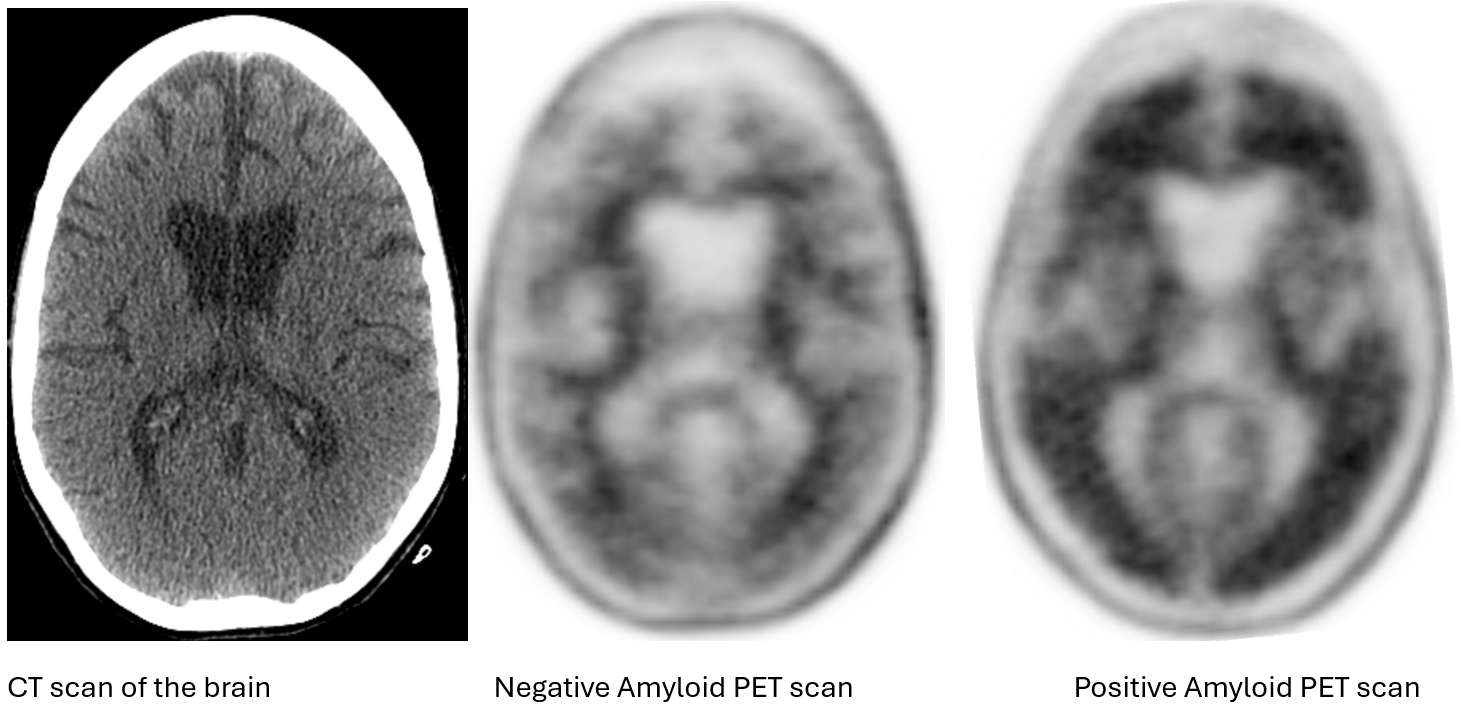

As of May 2025, either a positive Amyloid PET scan or positive cerebrospinal fluid (obtained by a spinal tap) is necessary to document amyloid pathology. An Amyloid PET scan is a nuclear medicine study, in which a patient is injected with a radioactive tracer that binds to amyloid plaque in the brain. It is normal for the tracer to bind to the lipid-rich deep white matter (center image). However, in abnormal amyloid PET scans, there is significant binding to the cortex, or surface, of the brain. The image on the right is a positive Amyloid PET scan. A patient with a positive Amyloid PET scan may qualify to receive the new anti-amyloid therapies that remove amyloid from the brain.